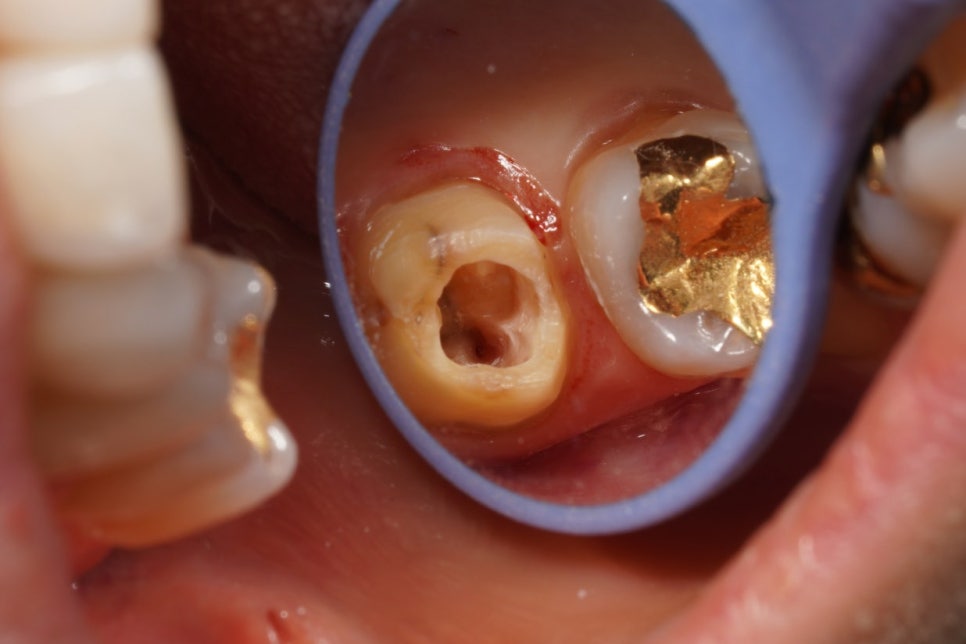

이전 치과에서 해놓은 AO가 좀 아쉽죠

치아 앞쪽을 너무 많이 파먹었습니다.

형태도 좀 아쉽네요

삼각형이 아니고 동그란 형태인 게.

근관도 안찾아놓으셨구

바쁜 치과였나봅니다.

미세한 신경관인 MB2는 없었습니다

다행히.

마무리도 잘 됐습니다.

코어 레진은 또 해서 보내드렸습니다

러버댐 건 김에 코어도 잘 하면 되잖아요